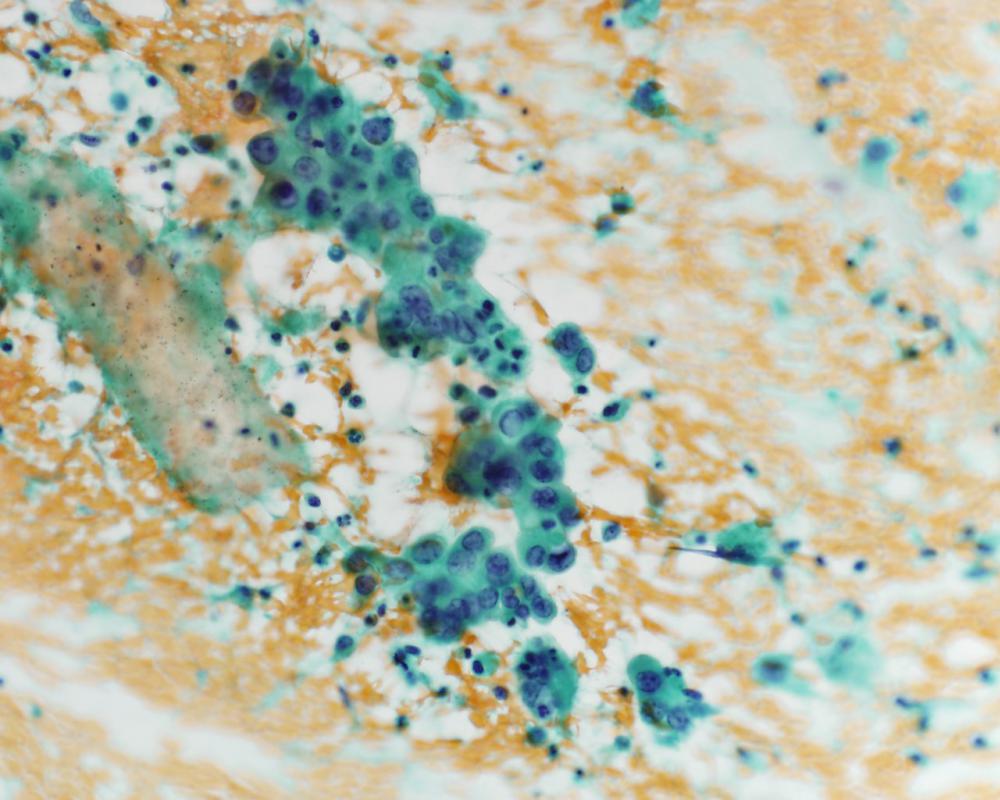

種別:泌尿器

| 年齢 | 68歳 | 性別 | 男性 |

| 採取部位 | 尿 | 採取方法 | 自然尿 |

臨床所見

既往歴:大腸癌

現病歴:S状結腸癌ならびに肺転移にて化学療法中。2週間前から排尿困難、残尿感があり、泌尿器科に紹介された。直腸診で前立腺は超胡桃大、全体に固く表面やや不整であった。精査のため、まず尿細胞診が行われた。

(画像2、5~8は同一の倍率です)

| 正解 | 1.大腸癌 |